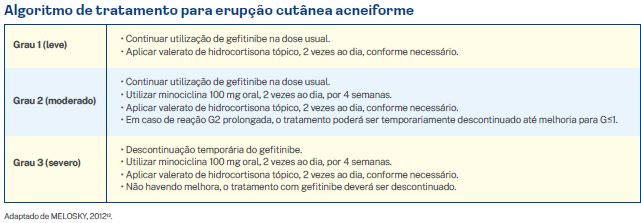

3.1.2. Erupção cutânea acneiforme

Uma série de medidas preventivas podem ser tomadas para reduzir o risco de erupção cutânea acneiforme induzida pelos EGFR-TKI.

Os pacientes devem ser instruídos a utilizarem cremes emolientes sem álcool ou perfume, 2 vezes ao dia. Protetor solar deve ser aplicado em áreas expostas ao sol, 2 vezes ao dia, para evitar queimaduras ou exposição excessiva ao sol, que podem piorar os sintomas de erupção cutânea. Banhos muito quentes e produtos que ressecam a pele devem ser evitados.